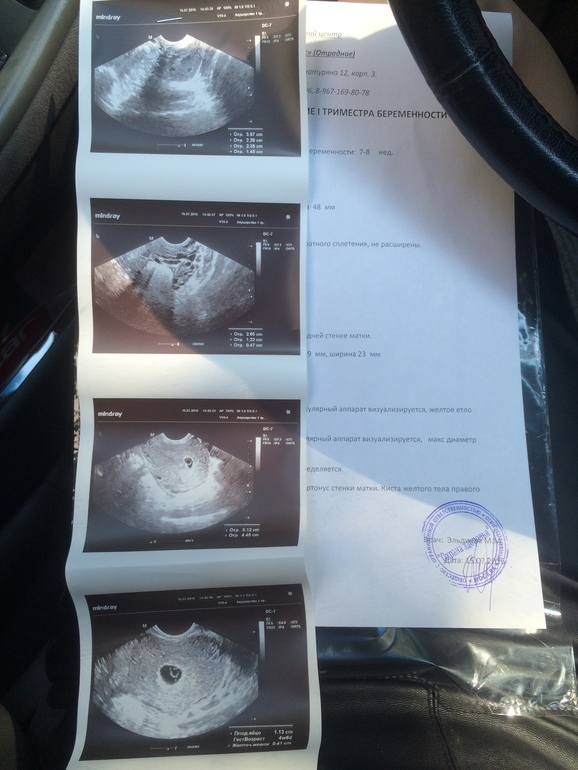

Писала утром про частое мочеиспускание и непрекращающиеся позывы в туалет, позвонила врачу своему, та сказала подождать час и вызывать скорую. Далее начались боли, схваткообразные и распирание влагалища. Срок 7-8 недель, только вчера была на УЗИ и не нашли эмбрион в плодном яйце, поставили под вопросом анэмбрионию и задержку в развитии плода. Вызвала скорую и не верится, что это конец.. Ведь ещё вчера все было хорошо.